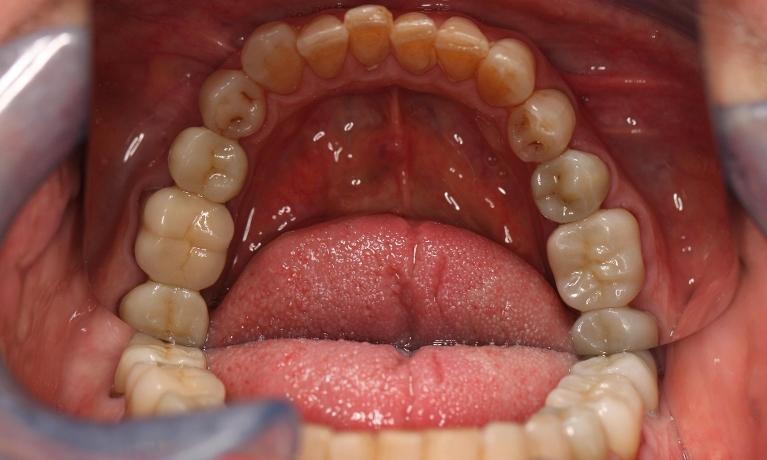

This man in his 50s was unhappy with the amalgam filling used to fix cavities. After discussing options, we agreed to fix his appearance by putting crowns on the teeth which create more of a natural look. This patient was very happy with the end result and is now in maintenance mode.